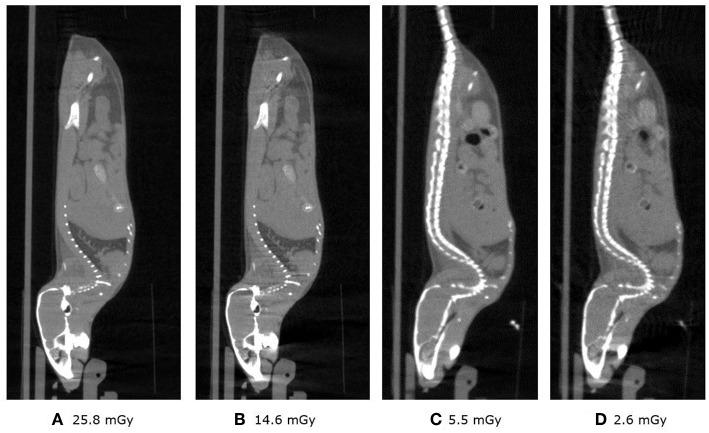

Ionizing radiation constitutes a health risk to imaging scientists and study animals. Both PET and CT produce ionizing radiation. CT doses in pre-clinical imaging typically range from 50 to 1,000 mGy and biological effects in mice at this dose range have been previously described. [F]FDG body doses in mice have been estimated to be in the range of 100 mGy for [F]FDG. Yearly, the average whole body doses due to handling of activity by PET technologists are reported to be 3-8 mSv. A preclinical PET/CT system is presented with design features which make it suitable for small animal low-dose imaging. The CT subsystem uses a X-source power that is optimized for small animal imaging. The system design incorporates a spatial beam shaper coupled with a highly sensitive flat-panel detector and very fast acquisition (<10 s) which allows for whole body scans with doses as low as 3 mGy. The mouse total-body PET subsystem uses a detector architecture based on continuous crystals, coupled to SiPM arrays and a readout based in rows and columns. The PET field of view is 150 mm axial and 80 mm transaxial. The high solid-angle coverage of the sample and the use of continuous crystals achieve a sensitivity of 9% (NEMA) that can be leveraged for use of low tracer doses and/or performing rapid scans. The low-dose imaging capabilities of the total-body PET subsystem were tested with NEMA phantoms, in tumor models, a mouse bone metabolism scan and a rat heart dynamic scan. The CT imaging capabilities were tested in mice and in a low contrast phantom. The PET low-dose phantom and animal experiments provide evidence that image quality suitable for preclinical PET studies is achieved. Furthermore, CT image contrast using low dose scan settings was suitable as a reference for PET scans. Total-body mouse PET/CT studies could be completed with total doses of <10 mGy.

电离辐射对影像科学家和实验动物构成健康风险。正电子发射断层扫描(PET)和计算机断层扫描(CT)都会产生电离辐射。临床前成像中的CT剂量通常在50至1000毫戈瑞之间,此前已描述过该剂量范围内小鼠的生物学效应。小鼠体内[F]FDG的剂量估计在100毫戈瑞左右。据报道,PET技术人员每年因处理放射性活度而受到的平均全身剂量为3 - 8毫希沃特。本文介绍了一种临床前PET/CT系统,其设计特点使其适用于小动物低剂量成像。CT子系统使用了针对小动物成像优化的X射线源功率。该系统设计集成了一个空间束整形器,与一个高灵敏度平板探测器以及非常快速的采集(<10秒)相结合,这使得全身扫描的剂量可低至3毫戈瑞。小鼠全身PET子系统采用基于连续晶体的探测器架构,与硅光电倍增管(SiPM)阵列耦合,并基于行和列进行读出。PET视野轴向为150毫米,横向为80毫米。样品的高立体角覆盖以及连续晶体的使用实现了9%(美国电气和电子工程师协会标准)的灵敏度,可用于低示踪剂剂量和/或进行快速扫描。全身PET子系统的低剂量成像能力通过美国电气和电子工程师协会标准体模、肿瘤模型、小鼠骨代谢扫描和大鼠心脏动态扫描进行了测试。CT成像能力在小鼠和低对比度体模中进行了测试。PET低剂量体模和动物实验证明,可获得适用于临床前PET研究的图像质量。此外,使用低剂量扫描设置的CT图像对比度适合作为PET扫描的参考。全身小鼠PET/CT研究可以在总剂量<10毫戈瑞的情况下完成。